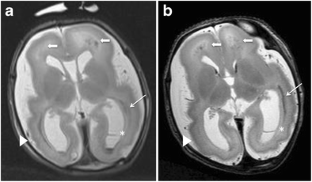

Fig. 1

Fig. 2

Fig. 3

Fig. 4

Fig. 5

Fig. 6

Fig. 7

Fig. 8